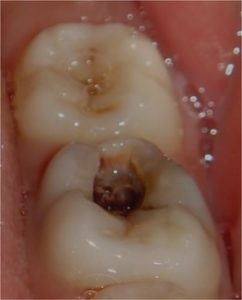

TREATMENTS

SERVICES

| SR. NO. | TREATMENT |

| 1 | Silver Filling |

| 2 | Calcium Hydroxide With SAF |

| 3 | Cement Filling / Dressing |

| 4 | Calcium Hydroxide With GIC |

| 5 | Composite Filling Light Cure |

| 6 | Miracle Mix |

| 7 | Gold Filling (Inlay) |

| 8 | GIC |

| 9 | MTA |

| 10 | Pin Retained Amalgam/ Bonded Restoration |

| 11 | Giomer |

| 12 | Composite Laminates- Direct |

| 13 | Indirect Composite Restoration |

| 14 | Metal Crown |

| 15 | Porcelain Facing With Metal Backing |

| 16 | Full Ceramic Crown |

| 17 | Post And Core (Cast) |

| 18 | Fibre Post Core |

| 19 | Root Canal Treatment Conventional |

| 20 | Rotary RCT |

| 21 | Root Canal Treatment With Thermafil |

| 22 | Root Canal Treatment With Obtura (II) |

| 23 | Root Canal Treatment With Calamus |

| 24 | Regenerative Endodontics |

| 25 | Surgical Endodontics (Microscope) |

| 26 | Crown Lengthening Procedures |

| 27 | Home Bleaching (Micro – Macro Abrasion) |

| 28 | Vital Bleaching (Zoom) |

| 29 | Vital/ Non Vital Office Bleach |

| 30 | X – Ray |